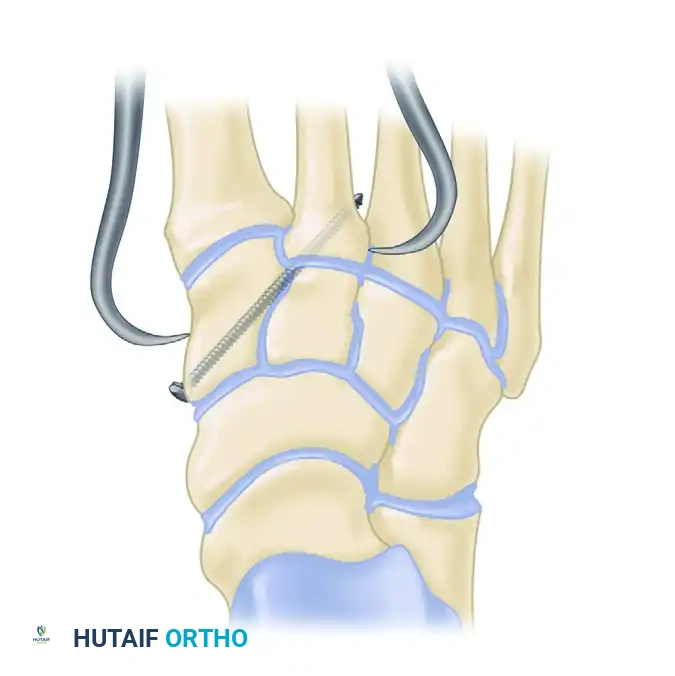

3. The "Homerun" Screw (Lisfranc Articulation)

- Under fluoroscopic guidance, reduce the second metatarsal base into its keystone slot between the cuneiforms. Hold this with a towel clip or reduction forceps.

- Pass a guidewire from the medial aspect of the medial cuneiform, aiming laterally and distally into the base of the second metatarsal. This trajectory mimics the native Lisfranc ligament.

- Overdrill and place an appropriate 4.0-mm or 4.5-mm cannulated screw over the guidewire to compress the interval.

4. Central Column Fixation (2nd and 3rd TMT)

- The second and third metatarsal-cuneiform joints are reduced and fixed similarly, typically with a single screw across each joint from dorsal-distal to plantar-proximal.

- If an intercuneiform screw is needed to stabilize the cuneiform complex, insert it under fluoroscopic guidance from the medial side of the medial cuneiform into the middle cuneiform.